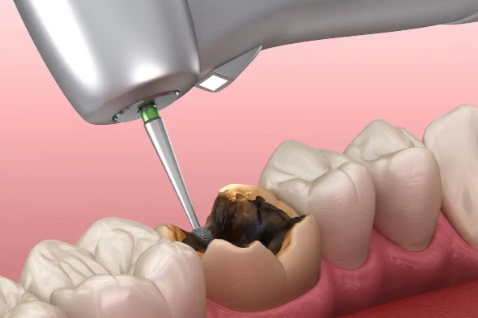

2、根管治疗补牙

当蛀牙深入到牙髓时,需进行根管治疗,治疗过程中可能需要分次进行。

显微镜根管治疗:1500元-3000元/颗

根管治疗步骤:检查→清理龋坏部分→测量根管→根管消毒→填充→戴牙冠。